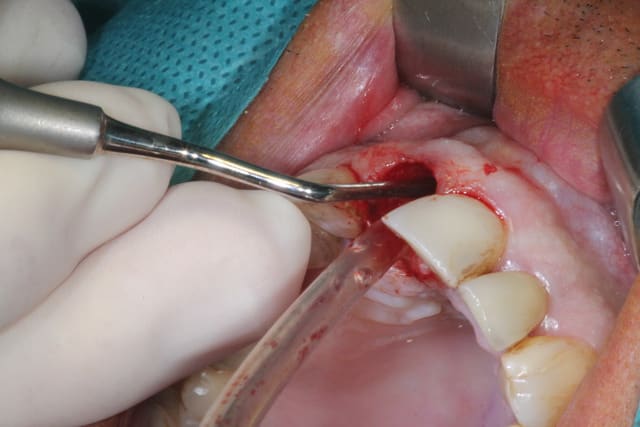

J'attendais d'avoir terminé le cas pour vous le présenter.

Il s'agit d'une EIIMCI avec comblement du gap.

J'ai utilisé un pilier plein que je n'ai pas déposé depuis la chirurgie.

Aurait-on obtenu le même résultat avec un pilier transvissé?

Pas d'infection en phase aiguë avant l'intervention, mais au vu de la fissure sur la racine et de la lésion osseuse, il devait y avoir quand même quelques bactéries.

J'ai bien cureté (manuel et rotatif), rinçage bétadine et métronidazole dans le mélange de biomatériaux.

Ça vaut ce que ça vaut, mais ça m'a paru correct sur le coup.